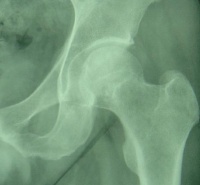

X线判断股骨头坏死

初期:髋关节间隙轻度增宽,以关节中下为主,主要因关节软骨增宽,股骨头外移所致,早期股骨头在外移2mm以内,晚期可达5mm,一般认为是关节旁及关节内软组织充血所致,可以逆转。

中期:股骨头皮质可以断裂形(台阶状)成角,基底处出现平行的双皮质征(双边征),其中台阶征及双边征是X线判断股骨头塌陷的早期征象,随后股骨头广泛脱位和碎解,其内可见死骨、裂隙、硬化和透光区,股骨头压缩变扁平,轮廓不规则,关节腔最初因股骨头变扁而增宽。股骨颈下方出现皮质增厚或骨膜增生,关节间隙可呈不规则变窄,髋臼关节面增生硬化,Sheaton线不连续,股骨头碎块可成为关节游离体。

晚期:股骨头骨结构完全消失,股骨头明显变扁或覃状变形,内有弥漫或局限性硬化或囊变区,关节间隙变窄,股骨头增粗,可有关节半脱位髋臼缘和股骨头基底部增生变成骨赘,髋臼关节面出现硬化并囊变,股骨头与髋臼变扁,股骨颈吸收,使下肢变短。

一、股骨头坏死的 X 线表现

初期: 髋关节间隙轻度增宽,以关节中下为主,主要因关节软骨增宽,股骨头外移所致,早期股骨头在外移2mm以内,晚期可达5mm,一般认为是关节旁及关节内软组织充血所致,可以逆转。

中期: 股骨头皮质可以断裂形(台阶状)成角,基底处出现平行的双皮质征(双边征),其中台阶征及双边征是X线判断股骨头塌陷的早期征象,随后股骨头广泛脱位和碎解,其内可见死骨、裂隙、硬化和透光区,股骨头压缩变扁平,轮廓不规则,关节腔最初因股骨头变扁而增宽。股骨颈下方出现皮质增厚或骨膜增生,关节间隙可呈不规则变窄,髋臼关节面增生硬化,Sheaton线不连续,股骨头碎块可成为关节游离体。

晚期: 股骨头骨结构完全消失,股骨头明显变扁或覃状变形,内有弥漫或局限性硬化或囊变区,关节间隙变窄,股骨头增粗,可有关节半脱位。髋臼缘和股骨头基底部增生变成骨赘,髋臼关节面出现硬化并囊变,股骨头与髋臼变扁,股骨颈吸收,使下肢变短。